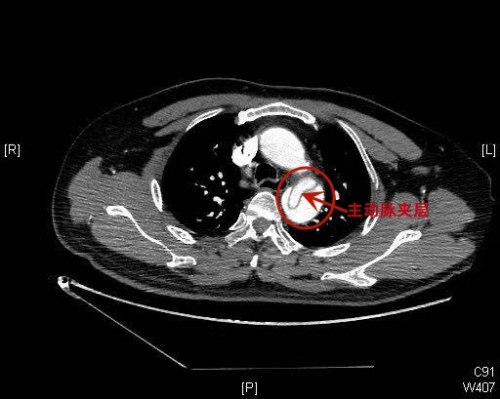

)急诊科。经相关检查后被诊断为主动脉夹层Stanford B型,是一种严重的心血管急危重症。据家属介绍,患者发病前正在给小学四年级的女儿辅导作业,患者因孩子做作业拖拉而情绪激动,随后就突然感觉胸腹部刀割样剧烈疼痛,有濒死感,倒在了沙发上,家人发现后立即拨打120急救电话,送入医院。

)急诊科接诊医生、副主任医师赫留党介绍,患者蒋耀龙(化名)入院时面色潮红,表情痛苦,已经出现嗜睡症状,血压达175/107mmHg(正常范围90/60-120/80mmHg),心率98次/分,呼吸54次/分。经检查,患者被诊断出主动脉夹层Stanford B型,累及腹腔干及左髂总动脉、左肾动脉,情况危急,迅速转入急诊ICU,并请外周血管介入科进行会诊。外周血管介入科主任、主任医师赵扬程会诊后,结合患者当前的身体状况建议先积极控制血压,待收缩压稳定至100-130mmHg,平均动脉压维持在60-70mmHg-+;心率稳定至60次/分左右后再行介入手术。

赵扬程主任介绍,主动脉夹层是一种严重的心血管急危重症,是由于主动脉腔内的血液从主动脉内膜撕裂处进入主动脉中膜,使中膜分离,形成夹层血肿,并逐渐延伸剥离主动脉的内膜和中膜,随时可能造成血肿破裂,被称为“不定时炸弹”。常见的临床表现为突发的剧烈的胸痛或腰背部疼痛,疼痛性质为撕裂样或刀割样,并伴有血压升高。动脉夹层的病因和危险因素有高血压、动脉粥样硬化等。据了解,该患者没有进行过系统体检,患有高血压而不自知,这次发病前由于辅导孩子作业情绪激动、出现血压突发性急剧升高而造成了主动脉夹层。如果治疗不及时,严重可造成相应脏器缺血坏死、功能衰竭甚至死亡。